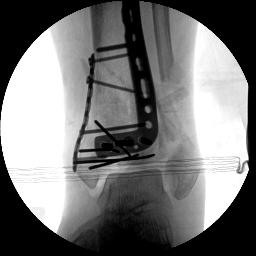

2.CO接骨機器人持續(xù)牽引維持復(fù)位,選擇前外側(cè)切口對前外側(cè)骨塊進(jìn)行撬撥復(fù)位,并用克氏針進(jìn)行臨時固定。C臂透視復(fù)位滿意,放置兩塊鋼板進(jìn)行固定。

3.在脛骨近端穿入一根克氏針,連接CO外固定架進(jìn)行固定,并外踝處穿入一根克氏針進(jìn)行固定。C臂透視位置滿意,縫合結(jié)束手術(shù)。

4.術(shù)后復(fù)查